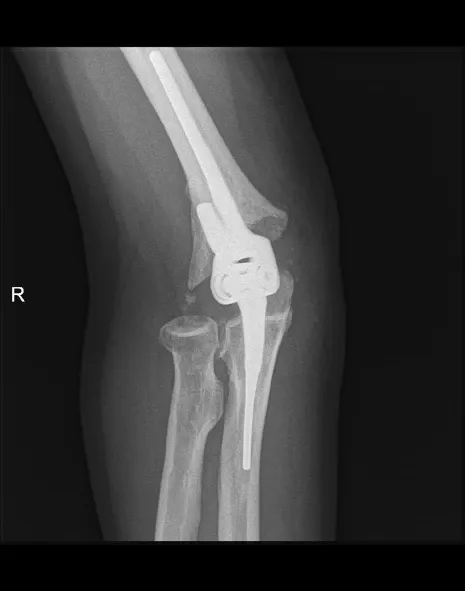

Elleboogartrose

Omschrijving

Elleboogartrose is slijtage van het kraakbeen, wat leidt tot ontsteking en pijn in de elleboog.

Klachten

- Pijn en zwelling

- Stijfheid en verminderde beweeglijkheid van de elleboog

- Soms nachtelijke pijn

Behandeling

- Pijnstillers, ontstekingsremmers, aanpassen activiteit/belasting van de elleboog

- Cortisone-inspuiting

Bij ernstige slijtage:

- Elleboogprothese

- Of radiuskopprothese wanneer slechts een deel van het gewricht is aangetast

Nabehandeling

Korte immobilisatie, daarna progressieve mobilisatie en vaak kinesitherapie. Revalidatie: 3 tot 6 maanden. Protheses geven meestal goede pijnverlichting; beweeglijkheid verbetert in mindere mate.